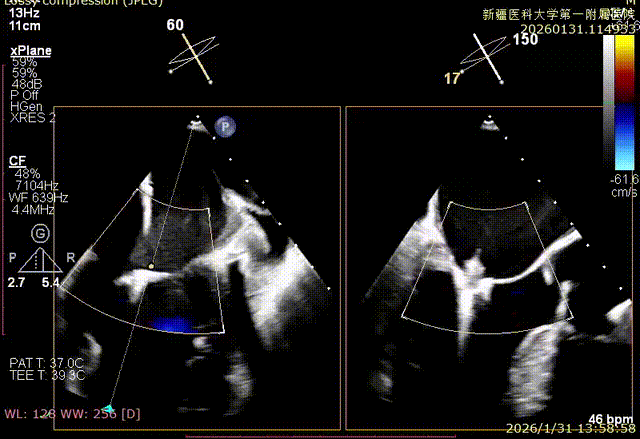

XPLAN后叶严重栓系

Bicom切面中重度反流

3D enface 观察后叶栓系

3D enface观察反流